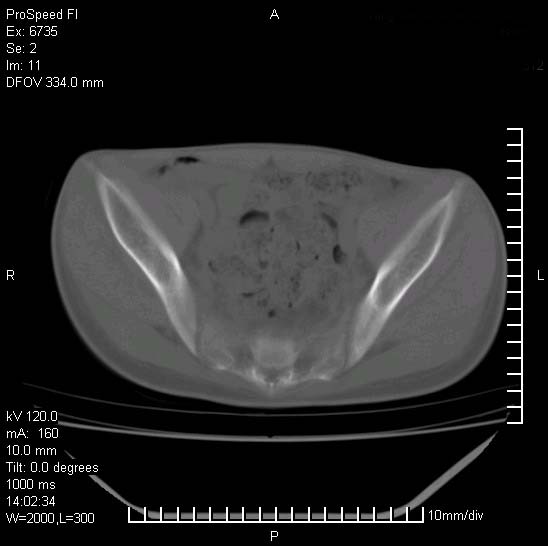

患者自诉胯部疼痛两年余,在当地服用中药,半月前至本院考虑骶髂关节结核,给予抗痨治疗。现发展至右下肢疼痛明显,活动受限,以膝关节处明显,拍膝关节平片无明显异常。

两侧骶骼关节改变,考虑强直性脊炎

左侧骶髂关节面限局性骨破坏,边缘硬化关节腔见钙化物;不出外tb

右侧骶髂关节也有类似改变,只是较左侧轻,首先考虑强直性脊柱炎,不除外结核,建议作hla-b27检查。

典型强脊炎改变,髋关节亦有累及

符合强直性脊柱炎表现。